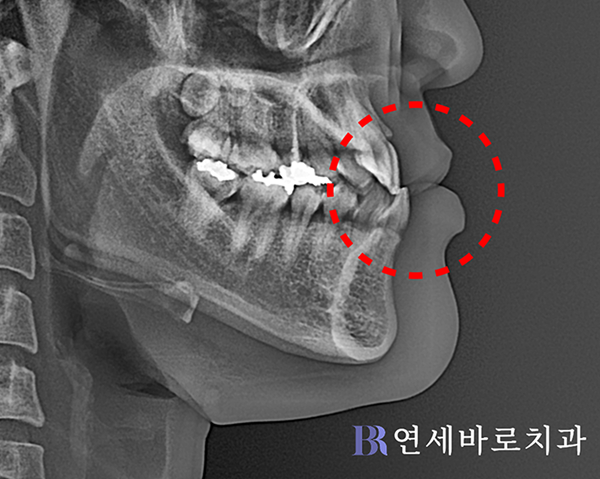

엑스레이 상으로 보아도

아랫입술이 살짝 나왔지만,

주걱턱은 비교적 경미한

수준에 그치고 있었습니다.

본인도 측면 안모에서는

특별한 콤플렉스가 없다면서

외모가 지나치게 변하지

않도록 해달라고 하셨습니다.